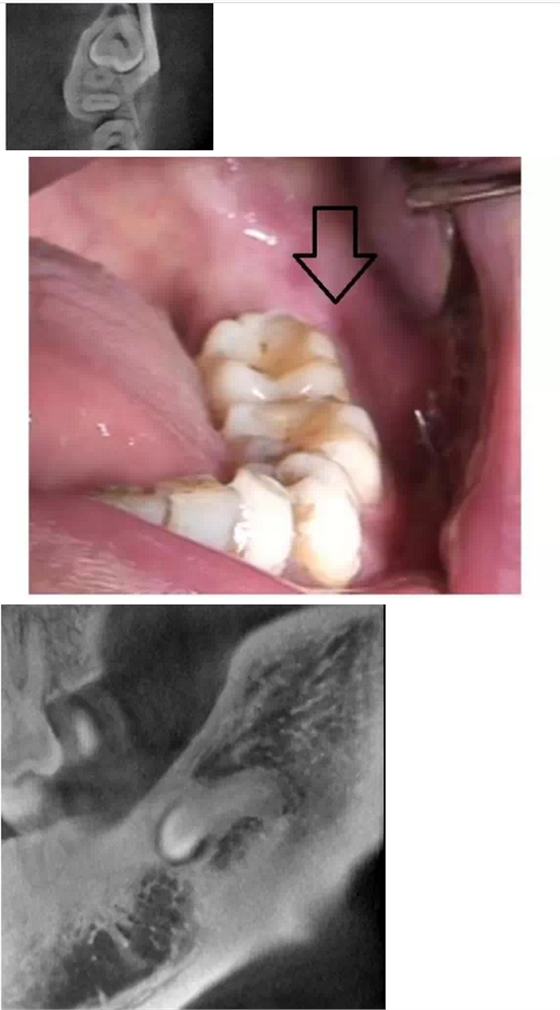

在拔牙一月后,鳥槍換大炮,診所引進(jìn)了三維CT,左側(cè)智齒在拍了CT后,前后頰舌上下關(guān)系就一目了然,此牙更難拔除,因?yàn)橥耆穹▓D二),其上面覆蓋有3mm厚的牙槽骨,其下緣與下牙槽神經(jīng)管緊緊相連,較危險(xiǎn);牙冠前緣與第二磨牙遠(yuǎn)中根也緊緊相連,后緣牙根向上翹;整個(gè)牙齒偏頰側(cè),頰側(cè)皮質(zhì)骨板較厚(圖三),舌側(cè)骨板也較厚,測(cè)好牙冠頸部上下距離約為9.5mm。

我們掌握了全方位的信息后,藉著CT向患者講解該牙齒的情況,患者充分理解拔牙的風(fēng)險(xiǎn)和醫(yī)生所需要的經(jīng)驗(yàn)和勇氣。因著有CT,術(shù)前的準(zhǔn)備更加充分:手術(shù)切口的設(shè)計(jì)和種植機(jī)去骨的部位選擇均在第二磨牙的遠(yuǎn)中頰側(cè)(圖四);車針長度的定位在9mm,防止磨到神經(jīng)管;掌握了牙根根尖部分是彎向下(圖五),就可以評(píng)估常規(guī)的挺子是很難進(jìn)去的,特別設(shè)計(jì)了四把不同角度的挺子。整個(gè)拔牙過程非常順利,行云流水,均在我們的掌握之中,猶如四驅(qū)的牧馬,人雖行駛在惡劣的沙漠地,仍是馳騁疆場(chǎng),酣暢淋漓。

第二顆智齒在CT的輔助下整個(gè)拔除時(shí)間比第一顆減少了一小時(shí),而且創(chuàng)口?。▓D六),術(shù)后反應(yīng)輕,患者在拔除的第二天胸悶的感覺就慢慢消失。